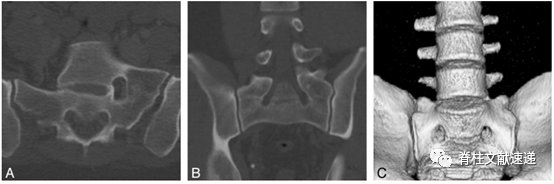

2、CT:传统上,LSTV常常是通过X线片来评估的。一些研究也应用了MRI,但是使用CT的研究非常少见。优于CT被认为是骨解剖的最佳成像方式,所以CT用来评估LSTV也是具有很大的优势的,特别是通过技术手段得到的三维重建结果(如图3),可以帮助我们更加直观的了解患者腰5横突的状态。

图3注:A:36岁女性IIIa型LSTV患者,轴向CT结果显示L5左侧横突与骶骨骨性融合;B:31岁男性IIIb型LSTV患者,冠状位重建CT结果显示L5双侧横突与骶骨融合。C:IIIB型LSTV患者三维重建CT结果显示L5双侧横突与骶骨完全骨性融合。